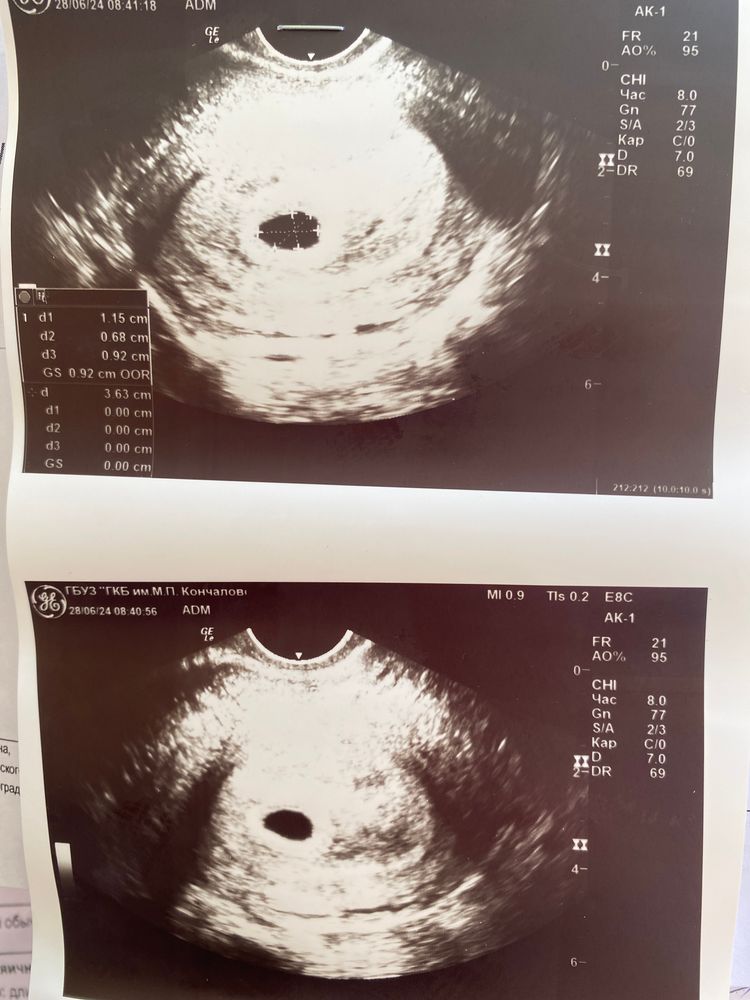

Доброе утро! Сегодня Была на узи. Плодное яйцо видно. Соответствует 5 неделям и 5 дням. Желтый мешок не определяется. Эмбрион не определяется.

Сказали придти на узи через 7 дней.